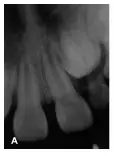

2牙冠異常,牙根較正常牙粗大,管腔大,根管內(nèi)有似牙釉質(zhì)牙本質(zhì)密度影像,中央有一空腔,形態(tài)似一小牙,內(nèi)陷根管根尖發(fā)育基本完成,主根管牙根形成2/3,根尖呈喇叭口狀,處于NollaVIII期,根尖周有低密度影像;2牙冠異常,處于NollaVI期(圖1A)。

圖1A:2,2牙冠異常,2根尖周低密度影像;